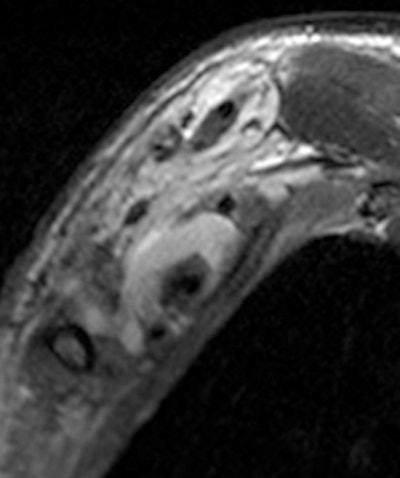

Young man who underwent a brachial plexus MRI examination following a motorcycle accident. A complex brachial plexus lesion is depicted. This case has been considered a true positive. All images courtesy of Dr. Alberto Tagliafico.

Patients ranged in age from 18 to 84 years. Their lesions detected by MRI represented a mix, including 35 root avulsions and brachial plexus cord injuries, 22 primary or secondary tumors, and four each entrapment syndromes, fibrous scars, and Parsonage-Turner syndrome.